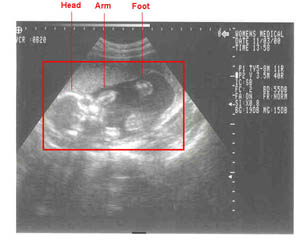

Ultrasound pictures of baby

11/03/2000--Head-on shots at 20 weeks. Weight approx. 1 pound.